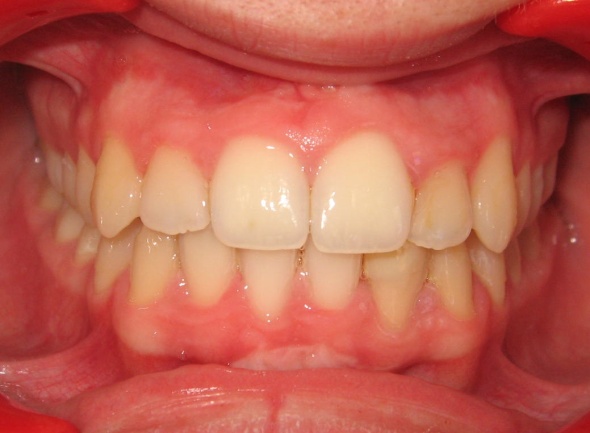

3 - Visage avant-après : un sourire retrouvé

Le sourire est nettement amélioré, grâce à une arcade élargie et des dents harmonieusement alignées. Le traitement a respecté l’esthétique faciale : le soutien des lèvres est conservé, l’angle naso-labial reste naturel. En évitant les extractions, on a préservé le volume labial et évité toute rétraction du profil. Ce résultat esthétiquement équilibré est aussi fonctionnel, sans compromis sur l’occlusion.